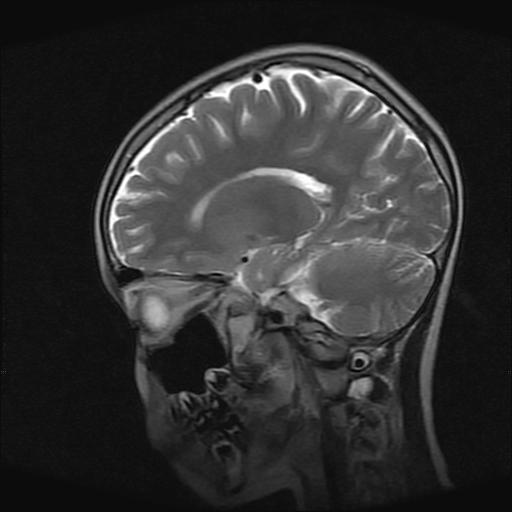

9岁女孩,三岁时诊断为癫痫,一直服丙戊酸钠,现患者一般情况良好,家长复查核磁片,看能否停药..

巨脑回

停药要结合临床,如无发作可以停。